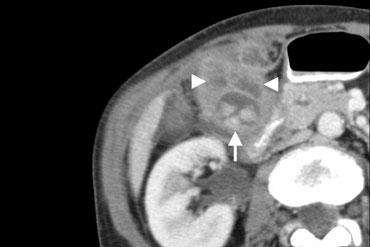

Bên trái là hình ảnh của bệnh nhân nam 62 tuổi với viêm túi mật cấp có sỏi.

Siêu âm cắt ngang tại vị trí đau tối đa cho thấy túi mật căng giãn do ứ dịch, thành dày, không thể ép xẹp (đầu mũi tên), với sỏi trong lòng túi mật và cặn lắng hoặc mảnh vụn.

CT có thuốc cản quang cho thấy viêm mỡ lan rộng (đầu mũi tên) bao quanh túi mật (mũi tên).